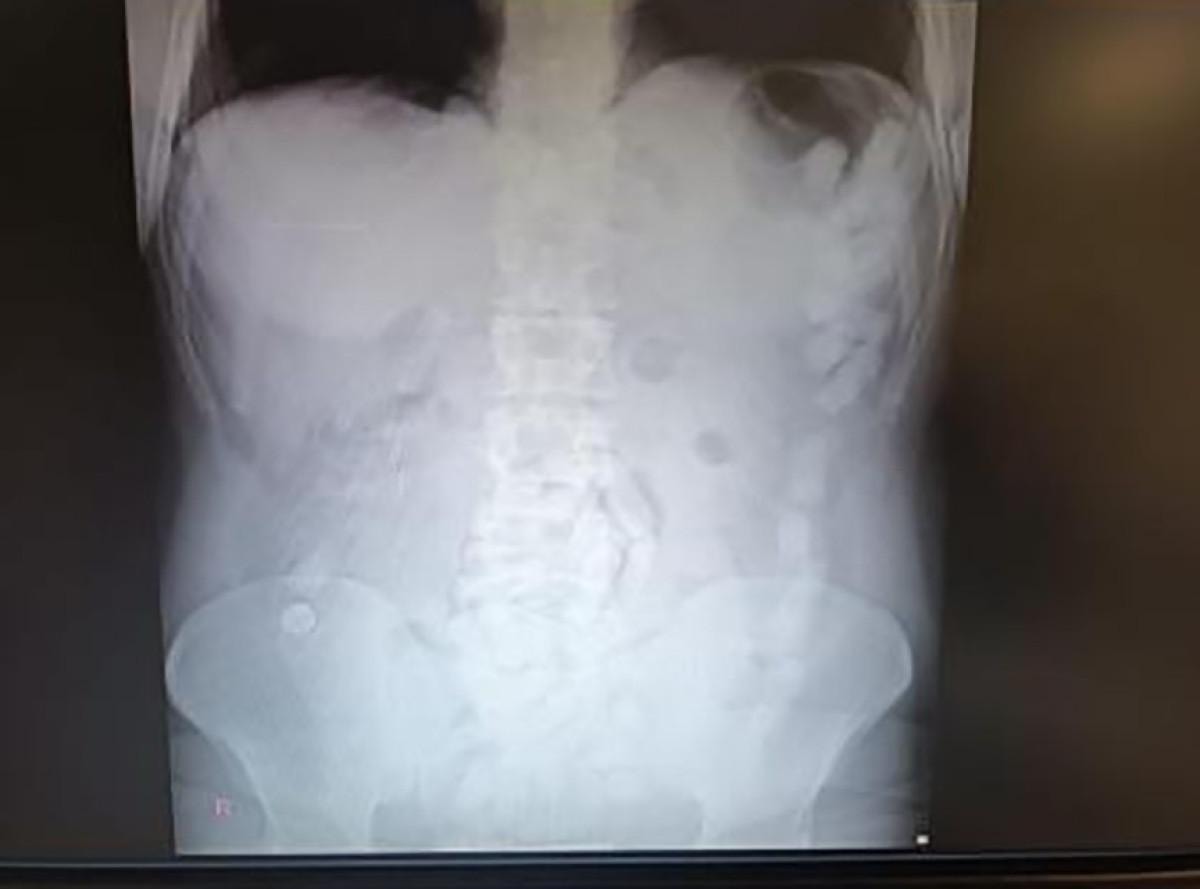

Kayseri Şehir Hastanesinde ultrason çekimi ile yapılan kontrolde şahsın midesinde çok sayıda kapsül olduğu tespit edildi.

Yapılan operasyonla şahsın midesinden çıkarılan 100 adet kapsülün içerisinde 729 gram uyuşturucu madde ele geçirildi.